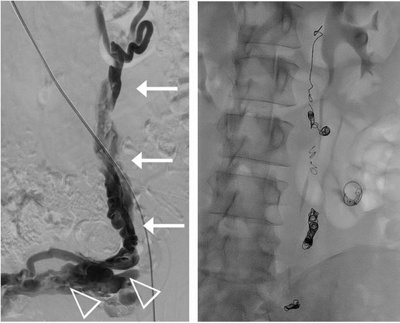

Darstellung der Krampfadern im kleinen Becken (Pfeilspitzen) sowie der erweiterten linksseitigen Eierstockvene (Pfeile), welche anschliessend mittels Sklerosierungsmittel und Metallspiralen (Coils) verschlossen wurden.